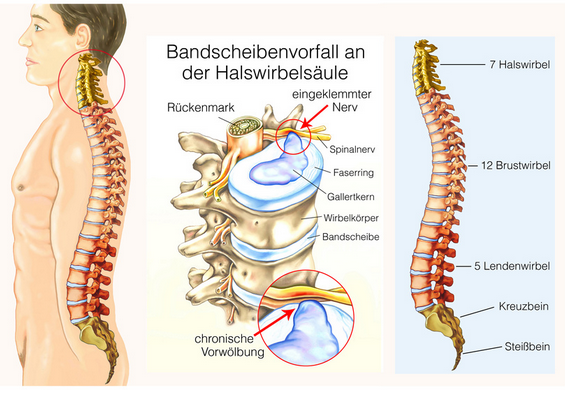

Bandscheiben sind die Druckpolster zwischen den Wirbelkörpern und ermöglichen — ähnlich wie bei einer Fahrradkette — eine Bewegung der sonst knöchernen Wirbelsäule vorwärts, rückwärts und seitwärts sowie eine Rotation. Bandscheiben haben keine Blutgefäße und ernähren sich durch Diffusion mit Nährstoffen aus der umgebenden Flüssigkeit. Ermöglicht wird das durch Druck und Sog. Wenn nun durch die Verspannung der Muskulatur ein Dauerdruck auf den Bandscheiben lastet kommt es zu Ernährungsstörungen — insbesondere des Faserringes, der den gallertartigen Kern ummantelt. Der Faserring reißt langsam ein, der gallertartige Kern wölbt sich an dieser Stelle vor und man spricht von einer/-m Bandscheibenprotrusion/-prolaps. Reißt er komplett durch kommt es zu einem Massenvorfall, der immer eine Akutintervention erfordert, da er auf das Rückenmark drückt. Bei Vorwölbung im Bereich des seitlichen Wirbelloches, wo der Rückenmarksnerv austritt kann es zu einer Kompression kommen. Bedingt durch die Lage der einzelnen Nervenfasern kommt es zunächst zu Schmerz, danach zu Gefühlsstörungen im Bereich des versorgten Gebietes (Dermatom) und letztendlich dann auch zu Muskellähmung, die immer eine sofortige chirurgische Intervention erforderlich machen.